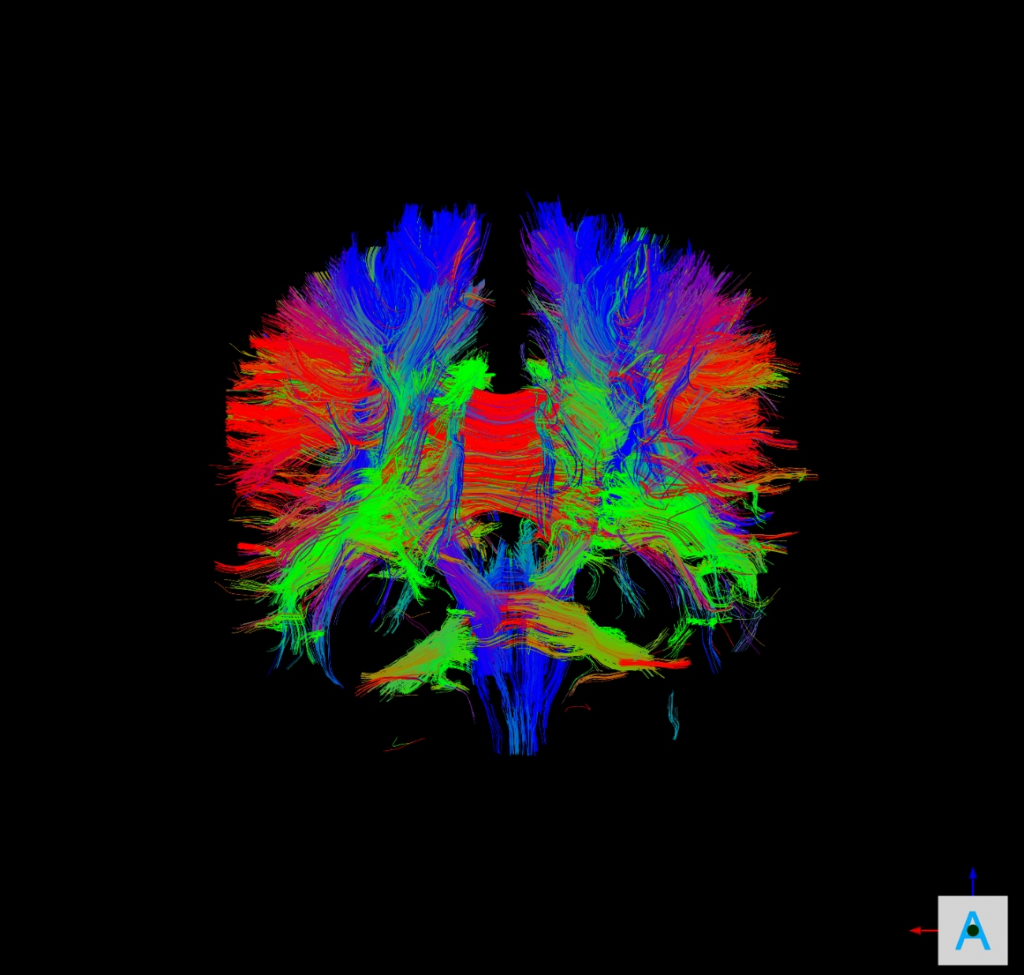

- 175mT/m/ms Gradient for ULTRA high-speed acquisition. 15% less time

Reduce acquisition Time with the Compression image method CSPI and obtain high resolution images with artifacts free with 6-8 times acceleration. For example reduce a SWI full head Image from 16 minutes to 3 minutes.

Clinical Images